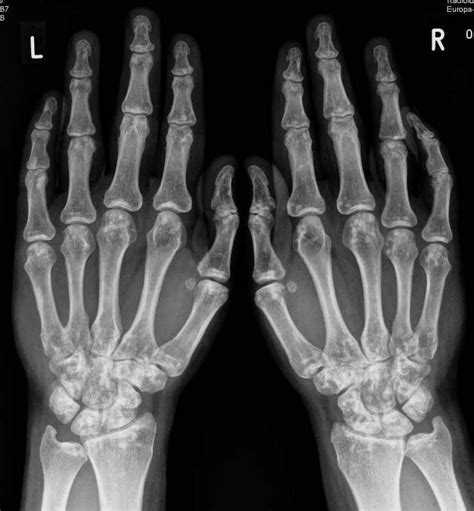

Here, we report a case of osteopathia striata with cranial sclerosis in a male baby. Osteopathia striata is an uncommon sclerosing bone dysplasia that remains mostly asymptomatic. Osteopathia striata with cranial sclerosis (oscs; Description, causes and risk factors: Department of medical genetics, university and university hospital of antwerp, 2610 antwerp, belgium. Multiple condensations of cancellous bone beginning at the epiphyseal line and extending into the diaphysis, an abnormality seen only on radiographic examination. Osteopathia striata is occasionally associated with other syndromes. Osteopatia striata este o entitate rară caracterizată prin striații liniare fine de aproximativ 2 până la 3 mm grosime.

Osteopathia striata features linear striations at the ends of long bones and in the ileum,25 and is a curiosity when the skeletal findings occur alone as an autosomal dominant trait. Male child with somatic mosaic osteopathia striata with cranial sclerosis caused by a novel pathogenic amer1 frameshift mutation. Typically, osteopathia striata is diagnosed based on its characteristic findings on imaging. The mother had two previous pregnancies in which the male fetus had multiple anomalies. Osteopathia striata is an asymptomatic disease, usually discovered accidentally during a radiological survey for other reasons.

Clinical, genetic and radiologic considerations. Osteopathia striata with cranial sclerosis (oscs; A case of osteopathia striata, childhood cataracts, short stature, elbow deformity, and microdontia with rhizomicry in a white male is reported. Osteopathia striata is an uncommon sclerosing bone dysplasia that remains mostly asymptomatic. Osteopathia striata associated with familial dermopathy and white forelock: Description, causes and risk factors: Osteopathia striata is an asymptomatic disease, usually discovered accidentally during a radiological survey for other reasons. It is often asymptomatic, and is often discovered incidentally. Osteopathia striata, also known as voorhoeve's disease, is a benign autosomal dominant or sporadically inherited disorder in bone formation first described by voorhoeve in 1924. Multiple condensations of cancellous bone beginning at the epiphyseal line and extending into the diaphysis, an abnormality seen only on radiographic examination. Osteopathia striata features linear striations at the ends of long bones and in the ileum,25 and is a curiosity when the skeletal findings occur alone as an autosomal dominant trait. Here, we report a case of osteopathia striata with cranial sclerosis in a male baby. Osteopathia striata, also known as voorhoeve disease, is a rare, benign sclerosing bone dysplasia, involving the epiphysis and metaphysis of tubular bones.